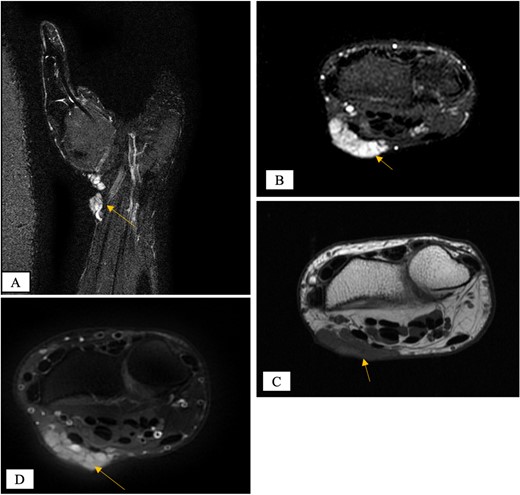

X-ray showed a well-defined non-aggressive lytic bony lesion of the first metacarpal bone (Fig. 1). Magnetic resonance imaging (MRI) showed a grossly stable skin and subcutaneous multilobulated soft tissue mass located at the palmar aspect of the wrist joint measuring 6 × 2 × 3.3 cm3 in its maximum anteroposterior, transverse and craniocaudal dimensions, respectively (Figs 2 and 3). The lesion showed low and high signals in T1 - and T2-weighted images with homogenous contrast enhancement. The lesion was inseparable from the flexor carpi radialis and palmaris longus tendons without definite invasion or encasement. The lesion was not in continuity, however, with the serpiginous lytic bony lesion noted at the first metacarpal bone exhibiting low T1 and high T2 signals with peripheral enhancement and no cortical destruction or associated soft tissue component (Fig. 4).

MRI coronal T2-weighted fat saturated image showing intraosseous lesion of high T2 signal in the first metacarpal bone.